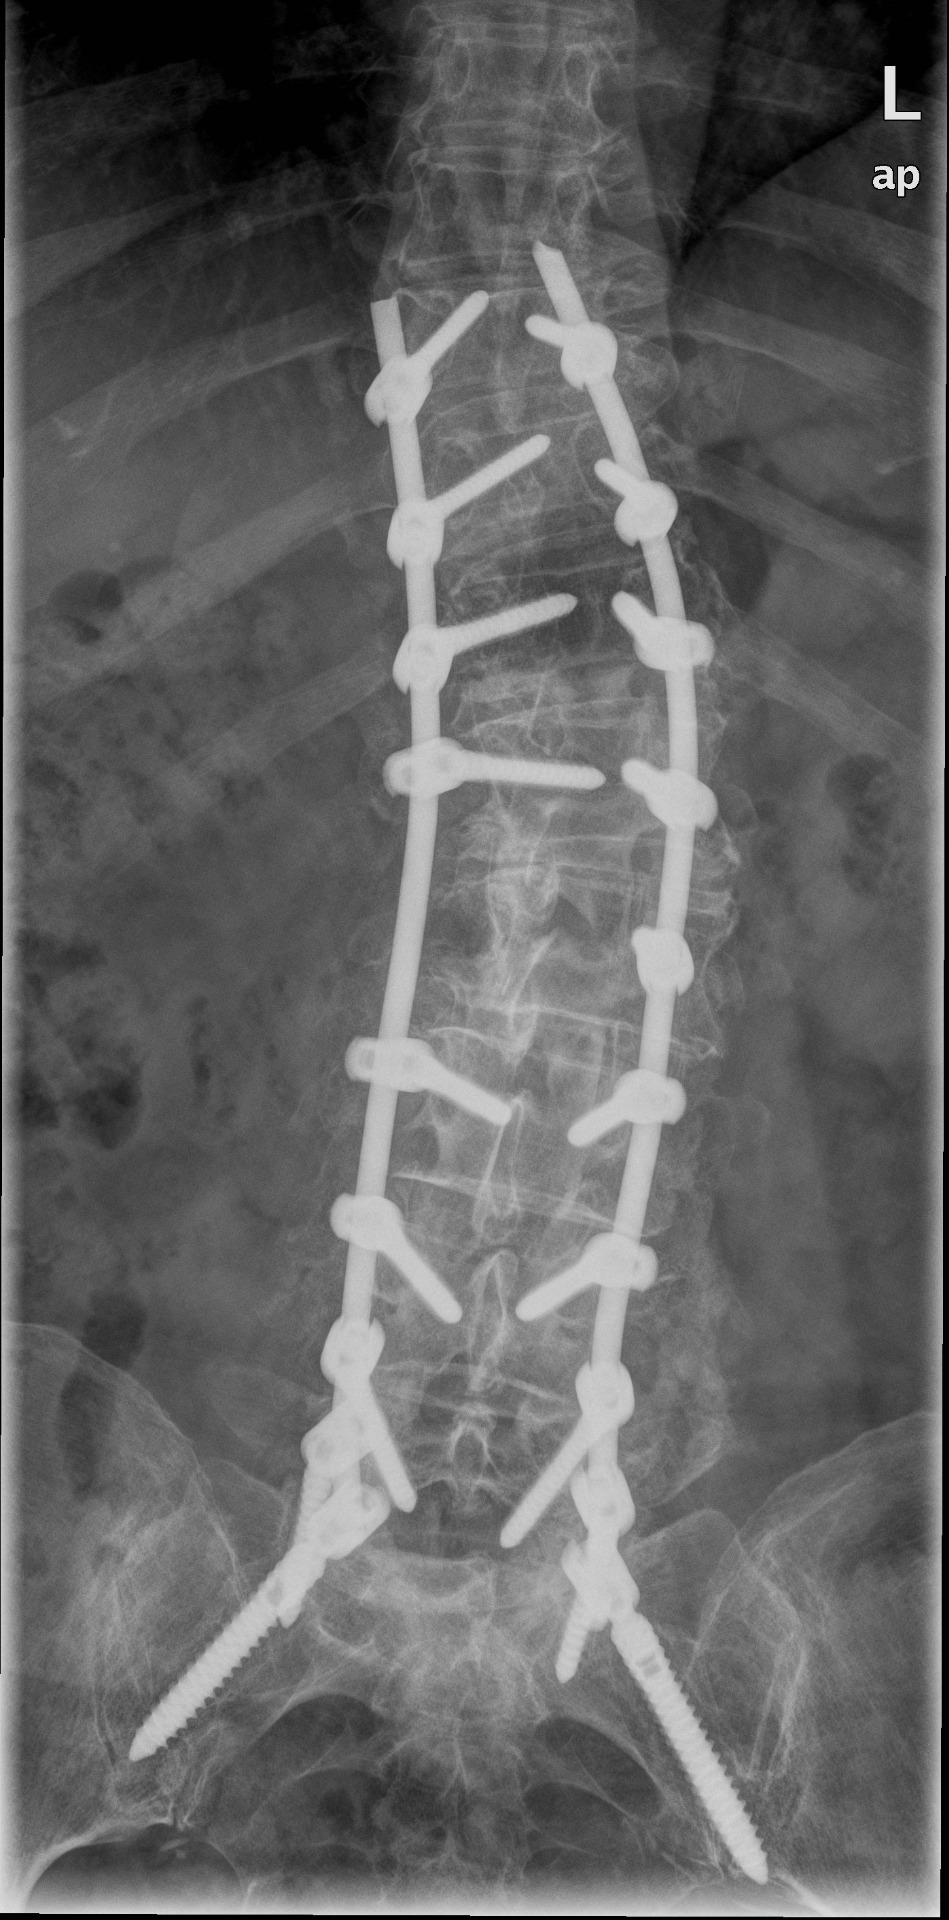

Pacientům nabízíme většinou odstranění útlaku nervových struktur s nebo bez stabilizace páteře, která má řadu variant, volených vždy individuálně podle dané patologie.